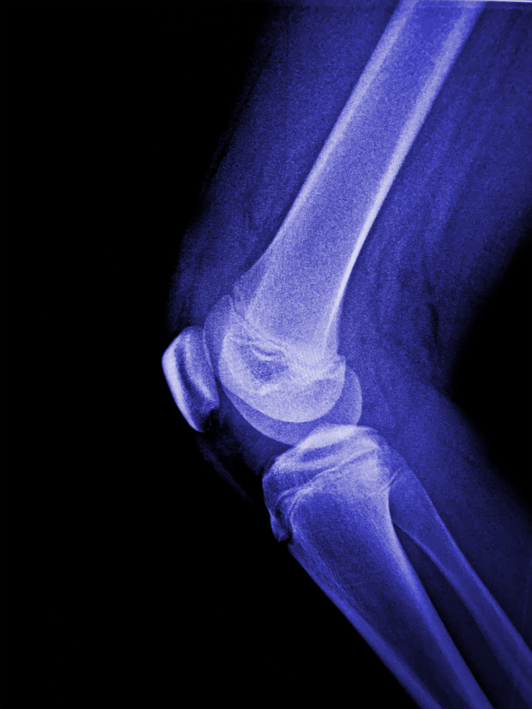

퇴행성 무릎 관절염

퇴행성 무릎 관절염은 무릎 관절의 연골이 마모되어 통증과 기능 장애를 유발하는 만성 질환입니다.

퇴행성 무릎 관절염은 무릎 연골의 지속적인 손상으로 인해 통증과 관절 기능이 악화되어 일상적인 움직임에 심각한 제약을 줄 수 있습니다.

치료를 지체하면 만성 통증과 관절의 변형이 발생하여 삶의 질이 크게 저하될 수 있습니다.

퇴행성 무릎 관절염은 나이가 들면서 무릎 관절의 연골이 점진적으로 마모되어 발생하는 질환으로, 주로 관절의 염증과 통증을 동반합니다. 이 질환은 운동과 일상 활동을 어렵게 만들며, 진행될수록 증상이 심해집니다.